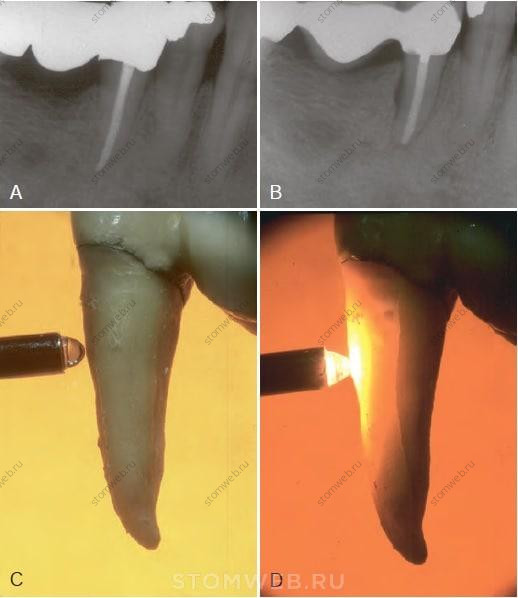

РИС, 21-6 Случай некроза пульпы вследствие трещины. Интактный зуб или зуб с минимальными реставрациями не должен быть девитальным. А) Данная рентгенограмма нижнего седьмого зуба с реставрацией на значительном расстоянии от пульпарной камеры; тем не менее, зуб не витален и симптоматичен. В) При исследовании жевательной поверхности обнаружена небольшая трещина на дистальном маргинальном гребне. С) После удаления зуба на мезиальной поверхности коронки и корня нет признаков трещины. D) На дистальной поверхности трещина распространяется на коронку и верхнюю часть корня. E,F) На разрезе хорошо видно, что трещина достигает пульпарной камеры.